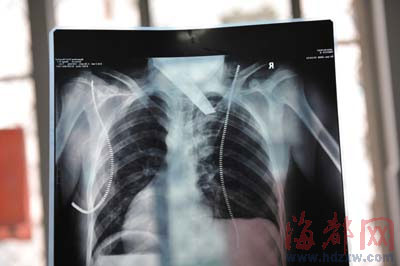

前晚,在第一醫(yī)院急救室,經(jīng)過4個多小時的搶救,醫(yī)生將匕首從小勇身上取出,發(fā)現(xiàn)這把匕首的刀尖扎斷了1厘米。由于小勇肺部被刺中,昨天上午,醫(yī)生再次進行了3個多小時的手術,切除了受傷的部分肺,直到下午,小勇才挺過來!巴α艘灰,現(xiàn)在總算醒了過來。”楊女士一夜沒睡,守在手術室外7個多小時,生怕兒子再醒不過來。不過,由于傷勢嚴重,小勇目前戴著氧氣呼吸,仍未脫險。